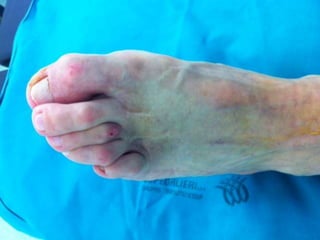

AR evolve in un danno alle articolazioni e porta a

progressiva disabilità con conseguenze sulla vita

quotidiana, tra cui impossibilità a compiere azioni

semplici come vestirsi oppure lavorare

50% dei pz riporta vari gradi di invalidità o non

autosufficienza entro 20 anni dall'esordio della

malattia

Le manifestazioni cliniche della malattia non

curata in modo ottimale portano a disabilità

nell'80% dei casi